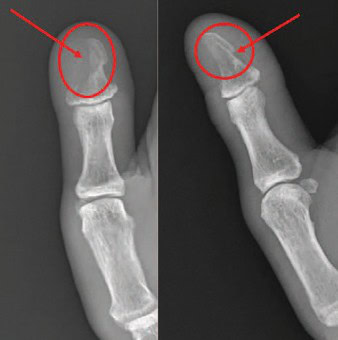

X-rays show soft tissue swelling and bony erosion of the distal phalanx, favoring osteomyelitis of the first digit. Osteomyelitis, a bone infection, can result from bacteremia or direct spread from adjacent joints or soft tissues. It can be either acute or chronic, and immunocompromised patients (particularly those with poorly controlled diabetes) are at increased risk. Osteomyelitis typically requires at least 1 cm of bone involvement (~40% mineral loss) to show on radiographs, with changes often visible 5–7 days after symptom onset in children and 10–14 days in adults. Magnetic resonance imaging is often required to confirm the diagnosis.